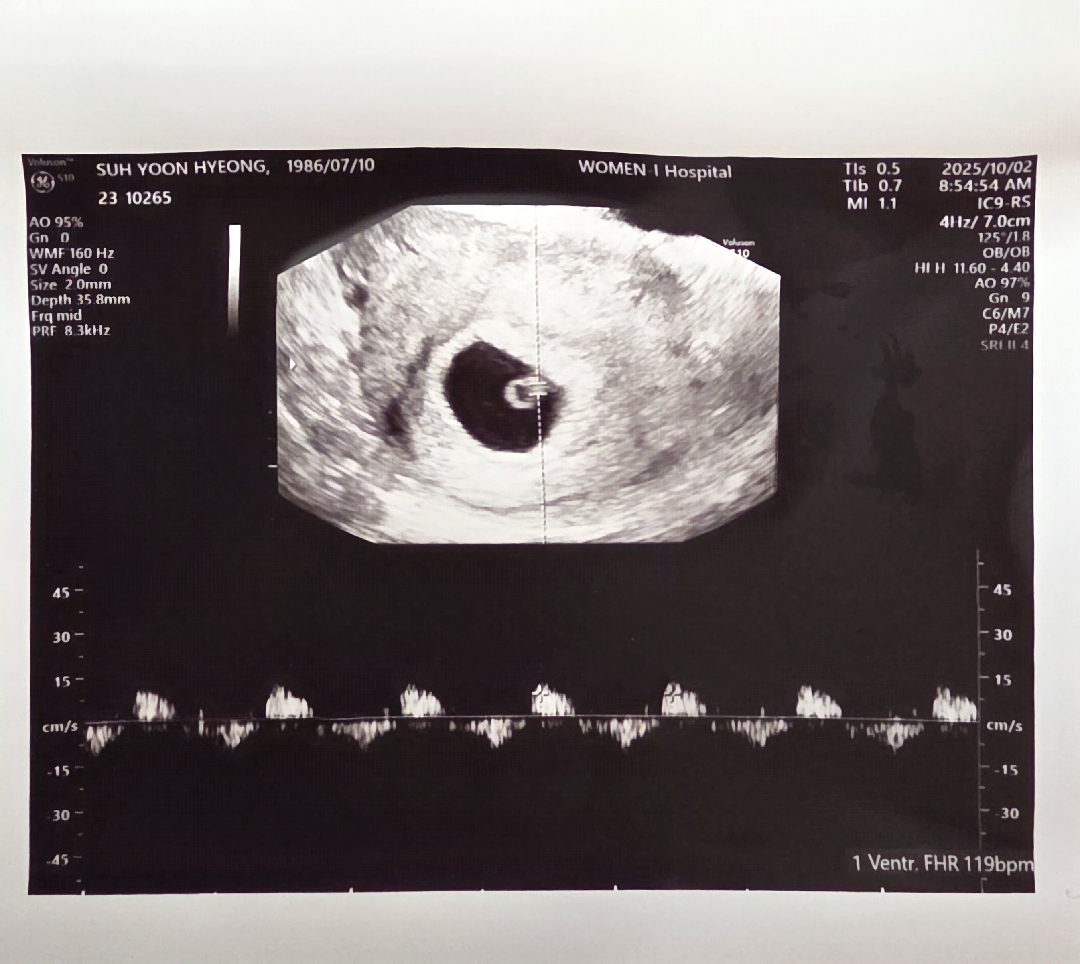

오늘 초음파 보고왔어요

저저번주 보고 왔을때 6주라고 했었는데 오늘 갔더니 다시 6주일이라고 하시더라구요ㅠㅠ 애기 크기로 봤을 때 6주 그대로라고 하시더라구요 애기가 작다고ㅠㅠ 제가 뭘 잘못하고 있는걸까요?ㅠㅠ

난임병원에서 자임은 힘들다고 했어서 기대도 안하고 있었는데 뜻하지 안데 찾아와준 축복이라 더 걱정이 되는것 같아요 이것저것 열심히 알아보고는 있지만 아직 모르는게 더 많으니 불안함이 가시지 않는거 같아요ㅠㅠ

괜찬다고 해주시긴 했는데 그래두 먼가 제가 못하고 있는건가 걱정이 되네요ㅠㅠ